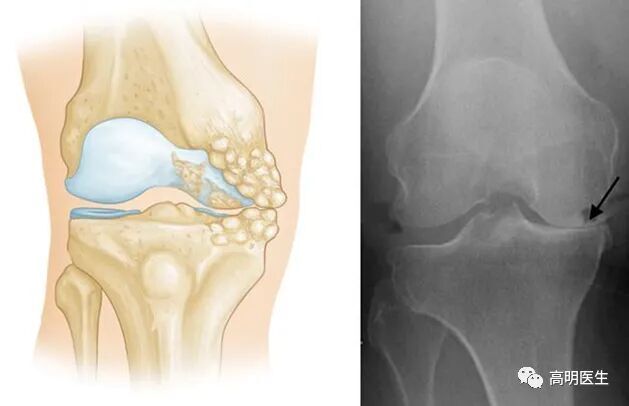

膝关节骨性关节炎,是一种膝关节的退行性疾病,主要临床表现为膝关节疼痛、肿胀及活动受限,主要病理表现为膝关节软骨的纤维化、磨损、剥脱等伴发滑膜充血水肿及骨赘增生等。

· 骨关节炎:最常见的类型,主要由关节软骨的退化引起。年龄增长、肥胖、过度使用关节、遗传因素等才是主要发病原因。

关节就像汽车轮胎,也有“使用寿命”。随着年龄增长,关节软骨逐渐磨损,弹性下降,最终出现骨赘(俗称“骨刺”),这就是骨关节炎的过程 。 只不过有些人的关节耐磨,有些人的不耐磨罢了。不仅人类,几乎所有脊椎动物都会得骨关节炎,但是对于一些关节负荷极小的动物(如蝙蝠、树懒等)发病率极低。这也说明骨关节炎是关节对磨损的自然反应。